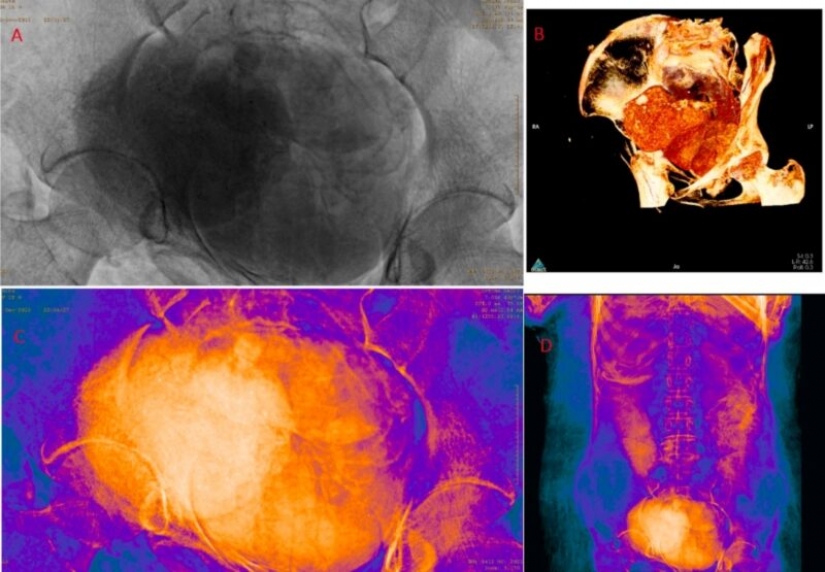

Para el nuevo estudio, los científicos decidieron escanear el cuerpo y se sorprendieron al encontrar que, de hecho, una mujer en el séptimo mes de embarazo está acostada en el ataúd.

Según los científicos, este es el único caso conocido de una momia egipcia embarazada bien conservada. Determinaron que la mujer tenía entre 20 y 30 años. Y el tamaño del cráneo fetal sugiere que estaba entre 26 y 28 semanas de embarazo.